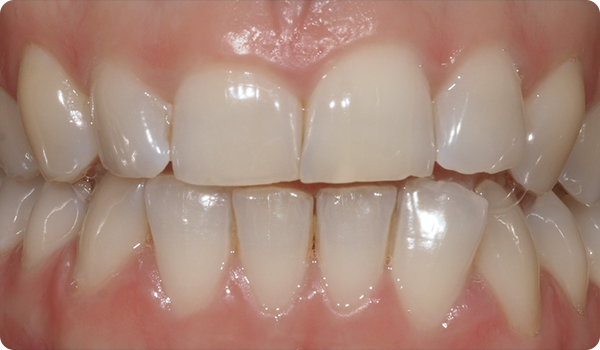

Het uitlijnen van de tanden met Right is de perfecte en meest conservatieve basis voor toekomstige whitening of fineerbehandelingen die de glimlach van de patiënt perfect maken.